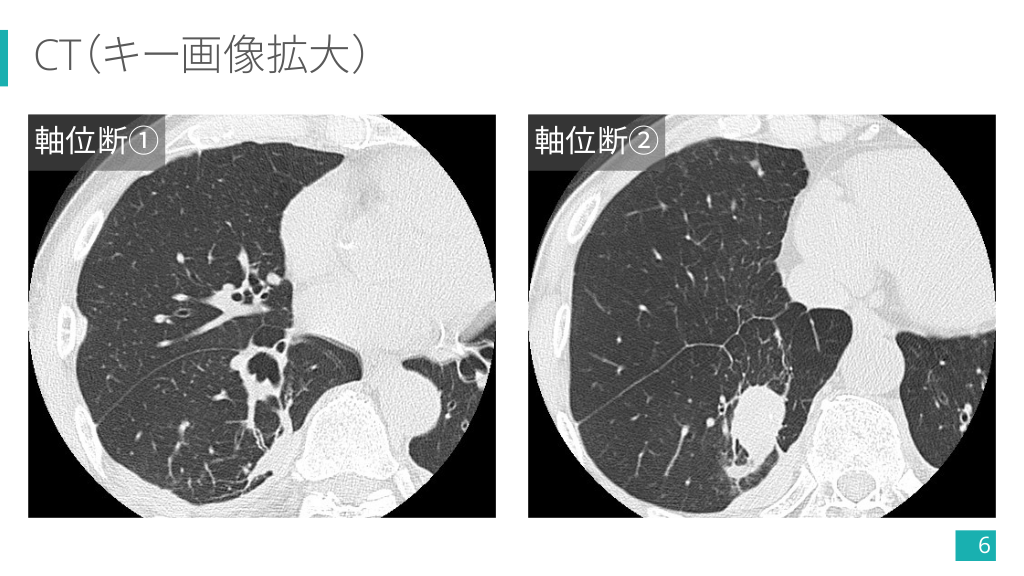

CT(キー画像拡大) 軸位断① 軸位断② 6

CT(キー画像) 多発胸膜プラーク(一部石灰化+) 右肺下葉の卵円形腫瘤 14

CT(キー画像) 腫瘤へと曲線的に収束する気管支血管束 (comet tail sign) 15

1-5) 円形無気肺の画像診断 Ø 肺野末梢に位置する円形/卵円形 の結節影・腫瘤影. Ø 肺の容積減少や胸水,胸膜プラー クなどの随伴所見を確認する. Ø 胸膜プラークは横隔膜面に着目!! 4) より引用 Case courtesy of Dr Matthew Lukies, Radiopaedia.org, rID: 45643 26

1-5) 円形無気肺の画像診断 Ø 両肺下葉に多い. Ø 単発 > 多発・両側性. Ø 2.5 cm 〜 5.0 cm 程度の大きさ のものが多い. Ø 経時的に増大せず縮小することも. Ø 胸膜プラークや石綿肺など アスベスト関連疾患の有無も重要. 4) より引用 Case courtesy of Dr Hidayatullah Hamidi, Radiopaedia.org, rID: 90658 27

1-5) 円形無気肺の画像診断 Ø 肥厚した胸膜から連続し,胸膜と 鋭角をなす円形/卵円形腫瘤. Ø 腫瘤に向かい,気管支血管束が曲 線的に収束する像 (comet tail sign) が特徴的. Ø 造影効果は様々. 5) より引用 28